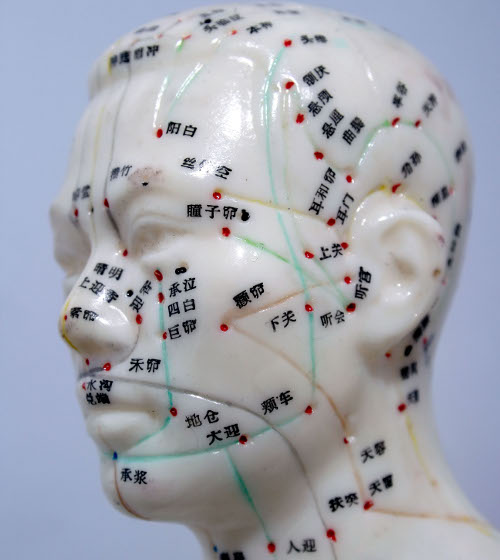

Gli aghi utilizzati nell’agopuntura aiutano ad alleviare i dolori grazie al fatto che innescano nell’organismo la produzione di una sostanza chimica, l’adenosina, di fatto un vero e proprio antidolorifico naturale.

Lo rivelano sulla rivista Nature Neuroscience i ricercatori del Center for Translational Neuromedicine presso il Medical Center dell’Università di Rochester, che inoltre suggeriscono come l’agopuntura potrebbe essere doppiamente efficace se associata ad una terapia a base di deossicoformicina, un farmaco antitumorale che sembra avere la capacità di mantenere alti i livelli di adenosina nell’area trattata.

Lo rivelano sulla rivista Nature Neuroscience i ricercatori del Center for Translational Neuromedicine presso il Medical Center dell’Università di Rochester, che inoltre suggeriscono come l’agopuntura potrebbe essere doppiamente efficace se associata ad una terapia a base di deossicoformicina, un farmaco antitumorale che sembra avere la capacità di mantenere alti i livelli di adenosina nell’area trattata.